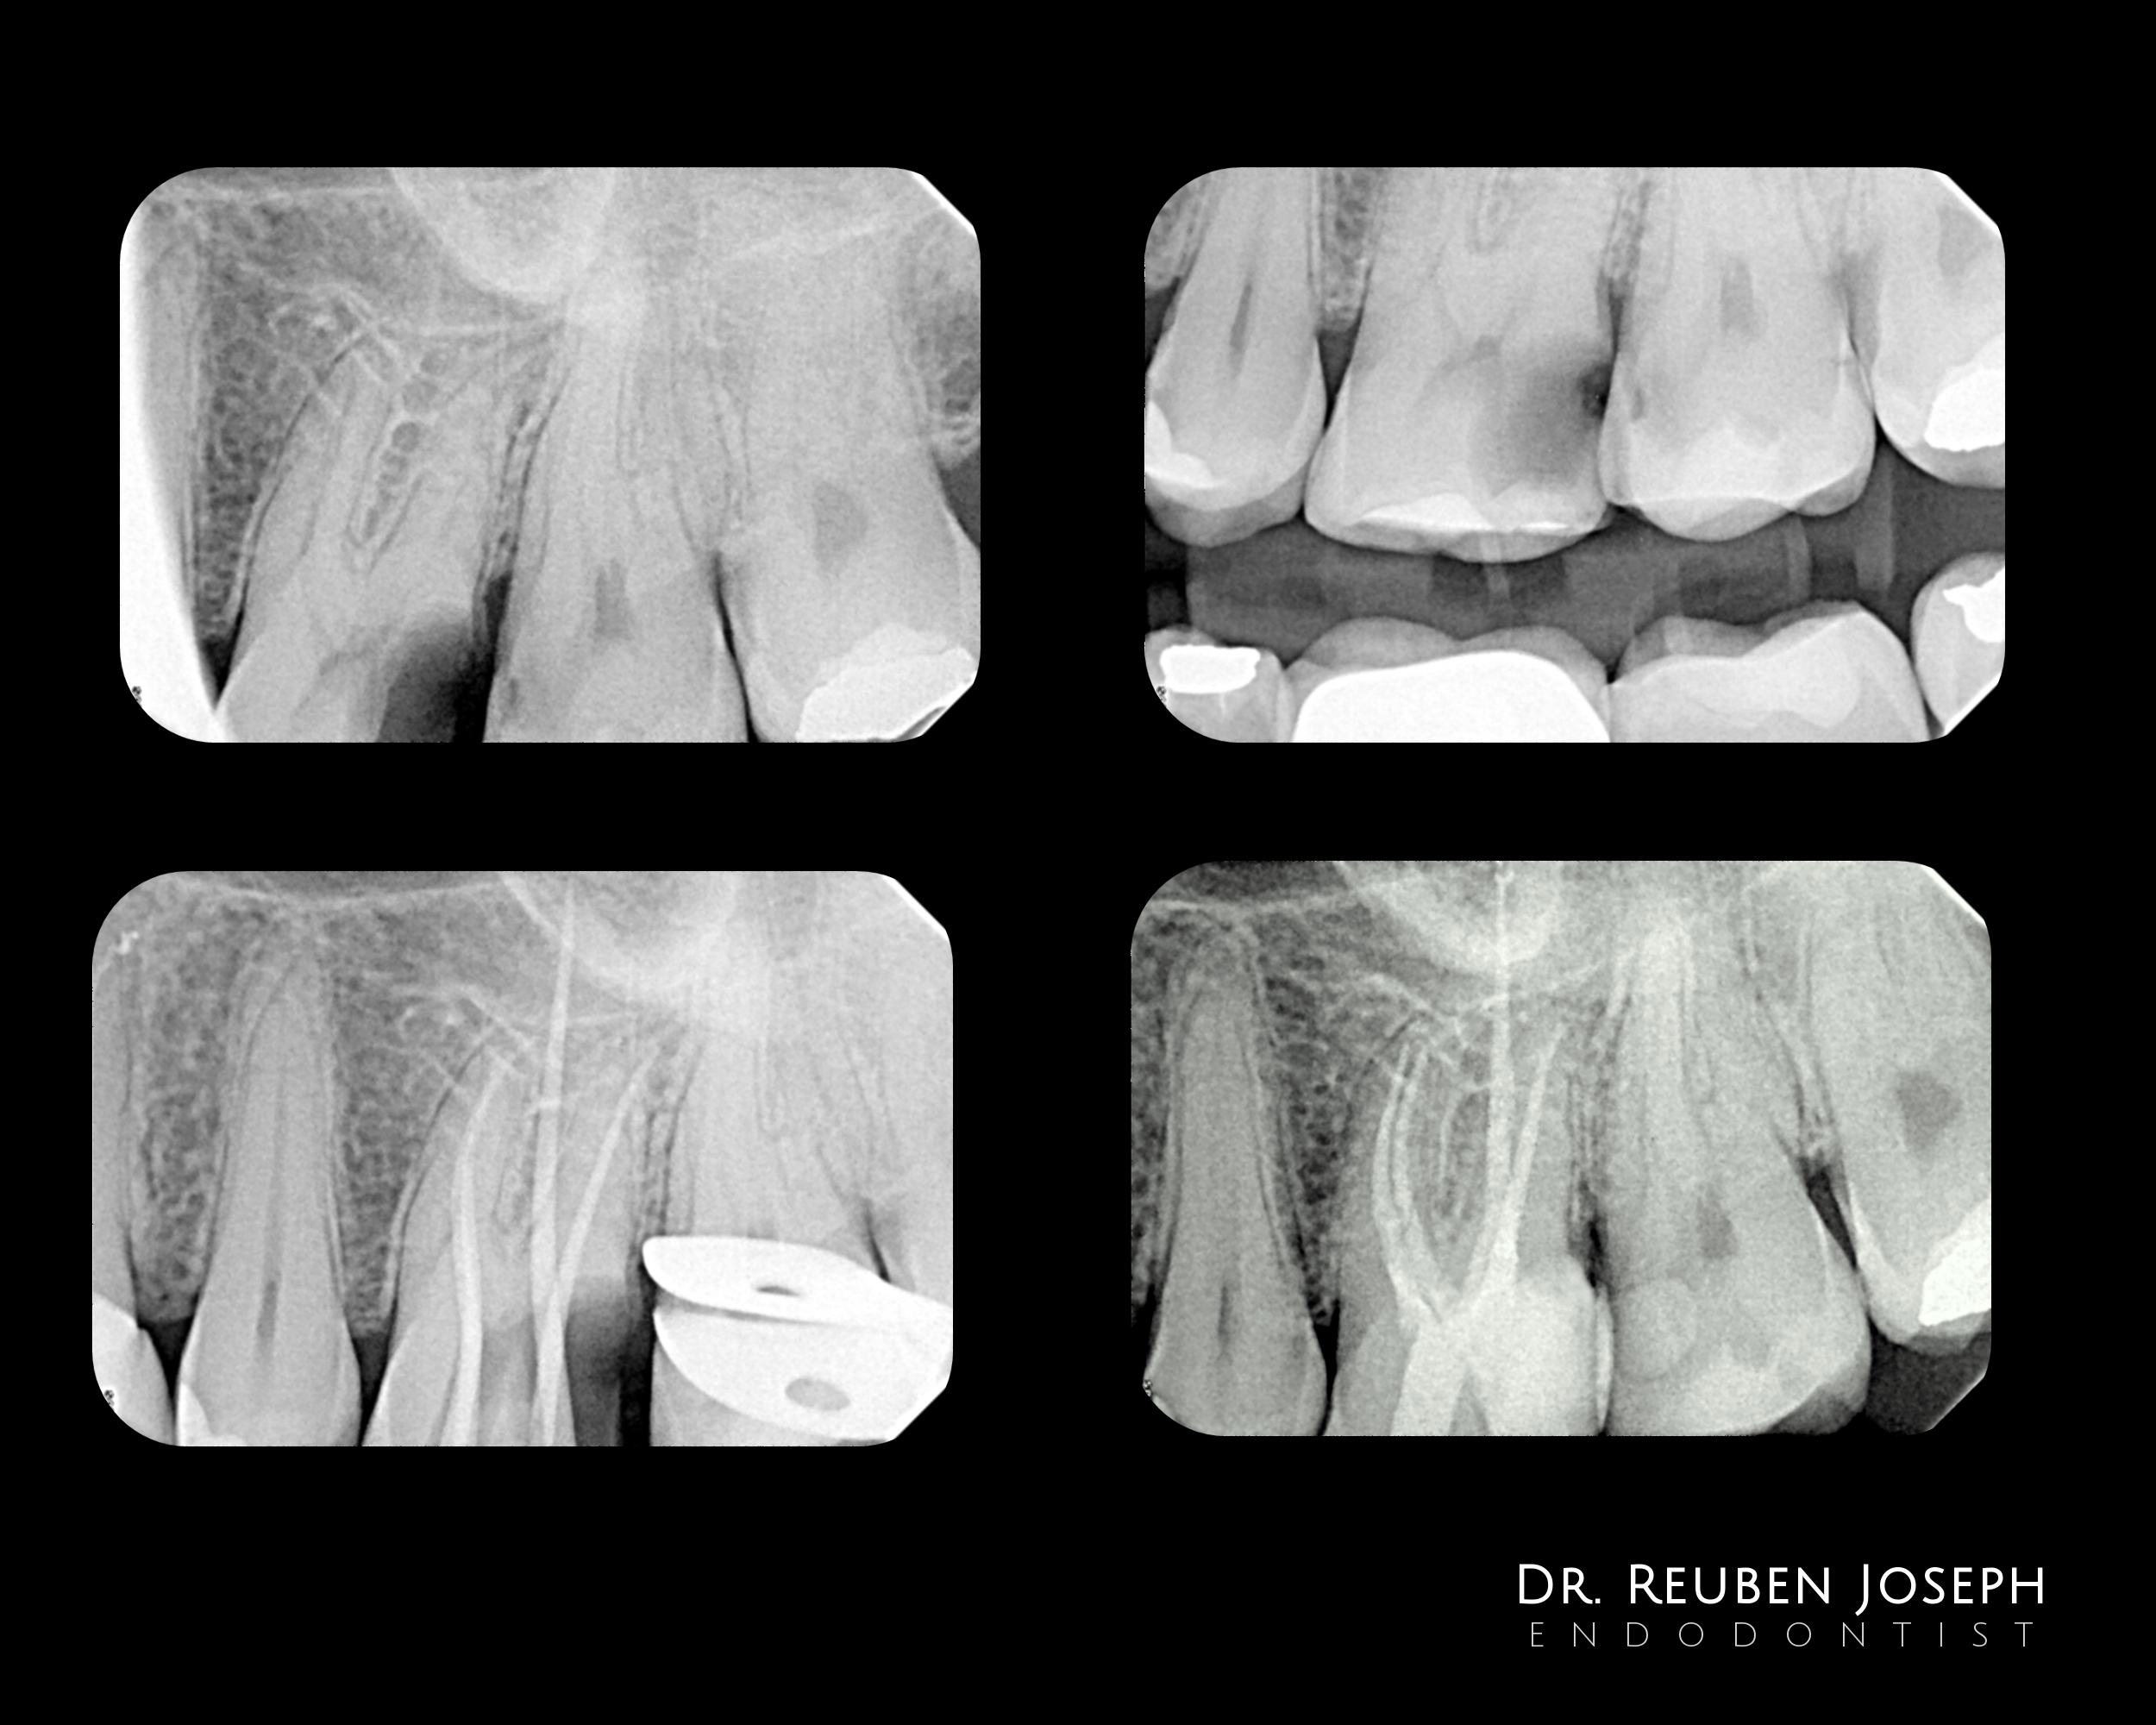

#14 RCT

Pre-op: Deep sub-gingival distal margin. Gingivectomy followed by margin elevation and isolation.

The usual shaping protocol and cleaning protocol. Obturated using WVC. Preserving the dentin bridge that extends buccal to lingual during post-endo prep might be a important consideration in this case.

This case highlights how critical dentin preservation is during RCT.